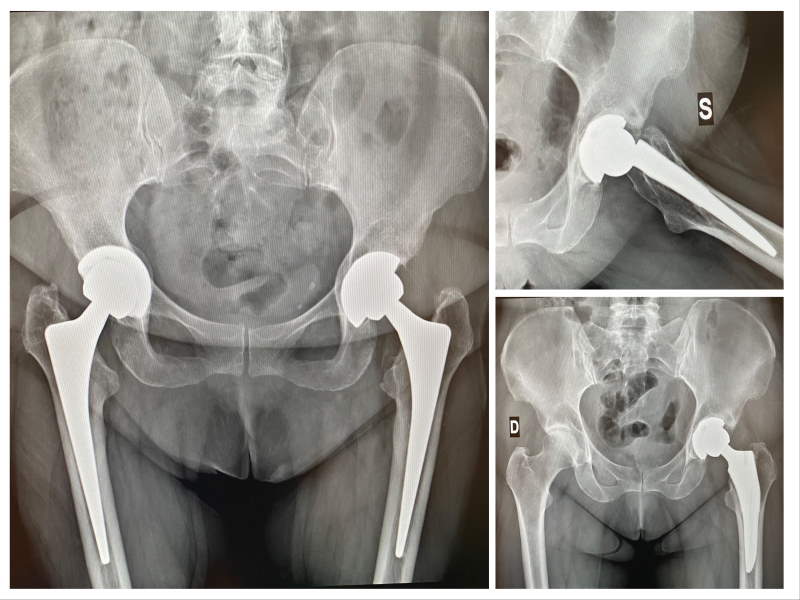

foto post chirurgico